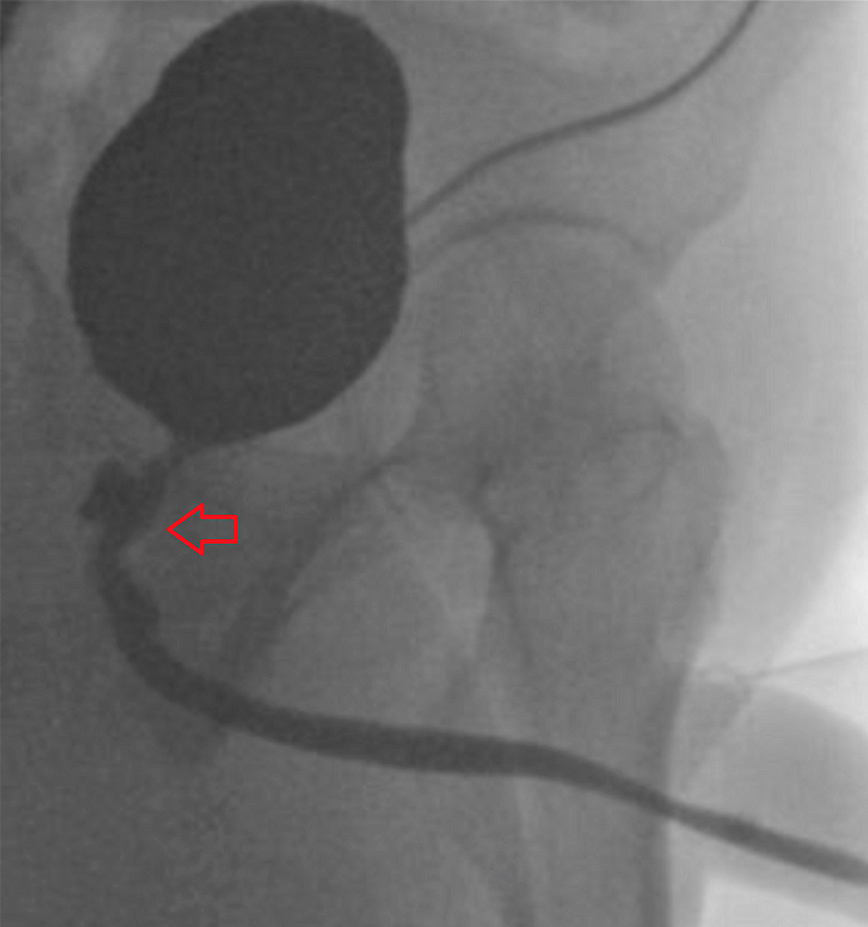

Περαιτέρω δοκιμές επιβεβαίωσαν την ύπαρξη ενός συριγγίου μεταξύ της ουρήθρας και του ορθού, από το οποίο περνούσαν τα διάφορα υγρά και στερεά. Εκτός από την επιδιόρθωση του συριγγίου μέσω χειρουργικής επέμβασης, η ομάδα αναζήτησε πιθανές αιτίες του προβλήματος.